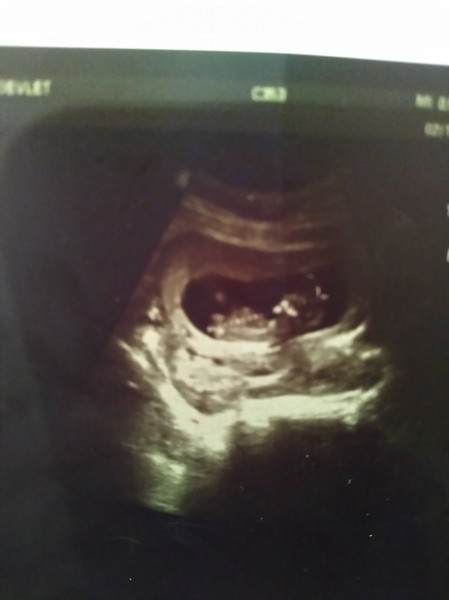

Kızlaaaar bende merak ediyorum cinsiyet tahmini nasıl yapıyorsunuz biliyorum çok çok erkendir ama insan merak ediyor tahmini fikri olan varmıdır

Gebelik haftası 11+5

Erkek canım fasulye şeklinde çünkü

Evet benimde ilk oğlumda dağınıktı kese birde erken canlanmıştı seninkide öyle, benim içimden erkek demek geçiyor, benimkininde eski ultrasonuna bakıyorum da aynı

Amin canım bak oğlumun ultrasonunu saklıyordum 11+3 teki ultrasonuna baktım bide seninkine aynı kese şekli herşeyi benimki erkek olmuştu